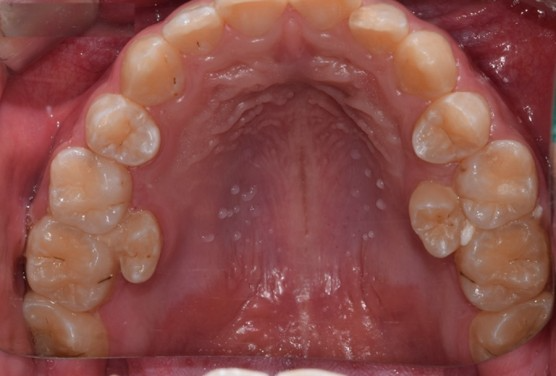

고등학생 남자아이의 입안입니다. 치아에 까만 점들이 보이죠?

정지우식이 될 가능성이 높은 충치

4개의 치아가 충치가 있긴하죠.

하지만 정지우식이 될 가능성이 높아 치료는 하지않고, 경과 관찰을 더하면 될 듯 합니다.

실제로 2년동안 충치는 그대로 잘 유지 되고 있습니다.